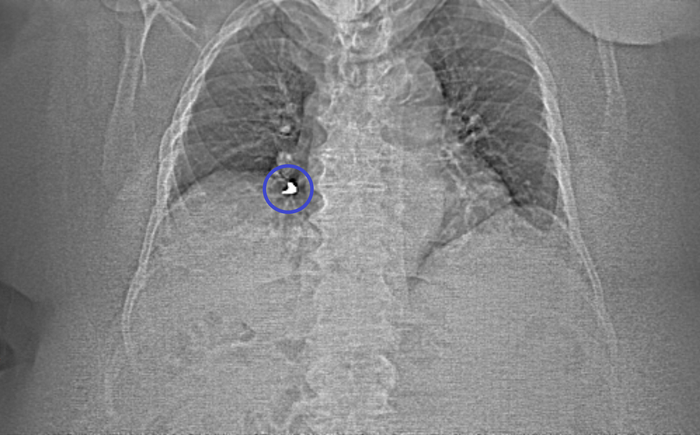

Переключаемся на "костное" окно (позволяет луче оценить кости и прочие плотные структуры), где реально видим "металлический" предмет в просвете правого нижнедолевого бронха:

сагиттальная, аксиальная и корональная реконструкция

Рестроспективно отмечаем этот предмет на топограмме (а-ля снимок части тела для дальнейшего планирования обследования):